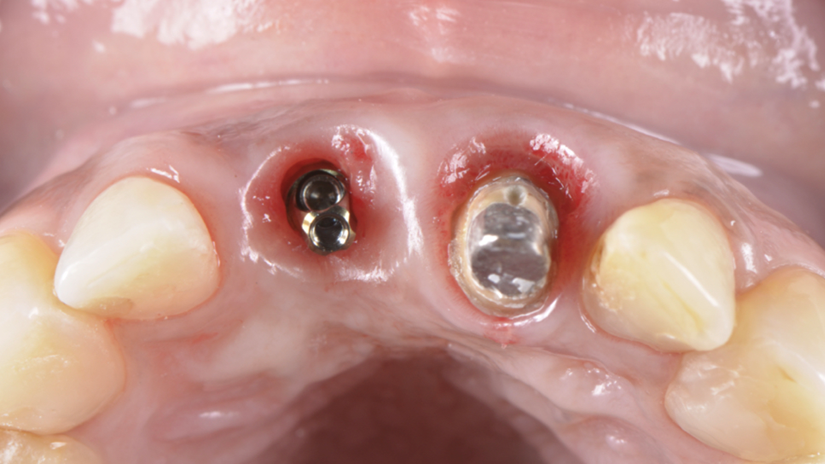

A paciente apresentava queixas estéticas e funcionais. Após avaliação clínica e radiográfica, optou-se pela substituição do pilar reto por um pilar Ideale angulado de 17 graus e 3,3 mm de diâmetro. Esse componente mais estreito e angulado permitiu corrigir o eixo emergente da futura coroa, viabilizando o planejamento de uma prótese parafusada na região estética.

O caso foi conduzido com planejamento cuidadoso, moldagens analógicas e provas clínicas. A reabilitação foi finalizada com a instalação de uma coroa metalocerâmica parafusada, garantindo estética, funcionalidade e reversibilidade do conjunto protético.